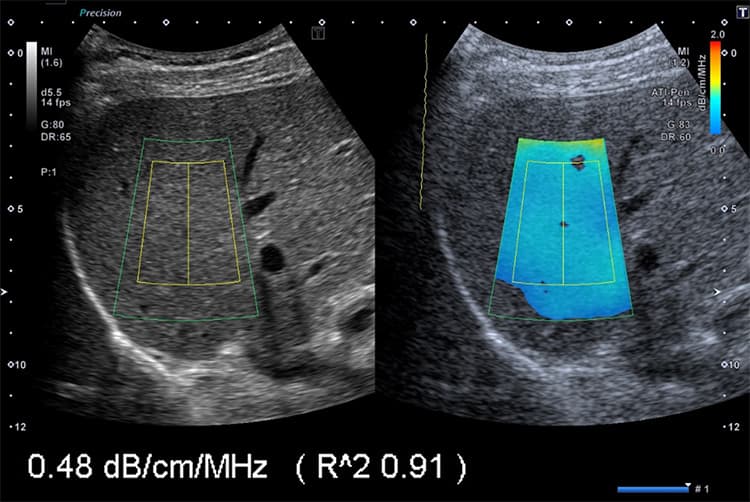

ATI(肝脂肪量を高精度に推定)

ATI(Attenuation Imaging)は、肝臓の脂肪量を正確に測定する方法です。従来の超音波検査では、脂肪肝の進行度を客観的に判断することまではできませんでした。一方ATIでは、脂肪肝を数値化することで客観的な評価が可能になります。

痩せている方も脂肪肝にかかることがあるため、外見だけでは判断が困難で、肝臓の状態を数値化できるATIは非常におすすめです。